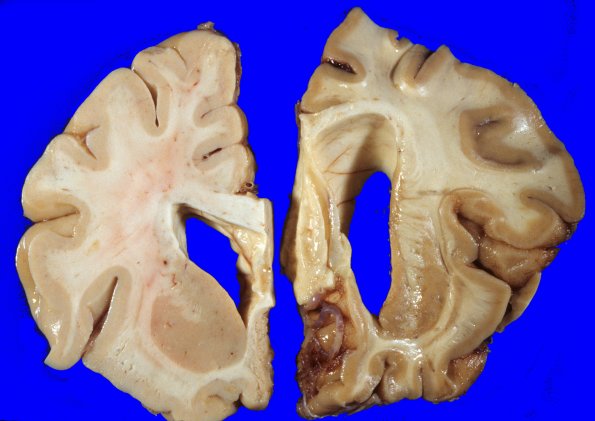

Coronal sections of the fixed basal ganglia show that the putamen is shrunken. The claustrum and globus pallidus appear somewhat small as well but are not appreciably discolored.